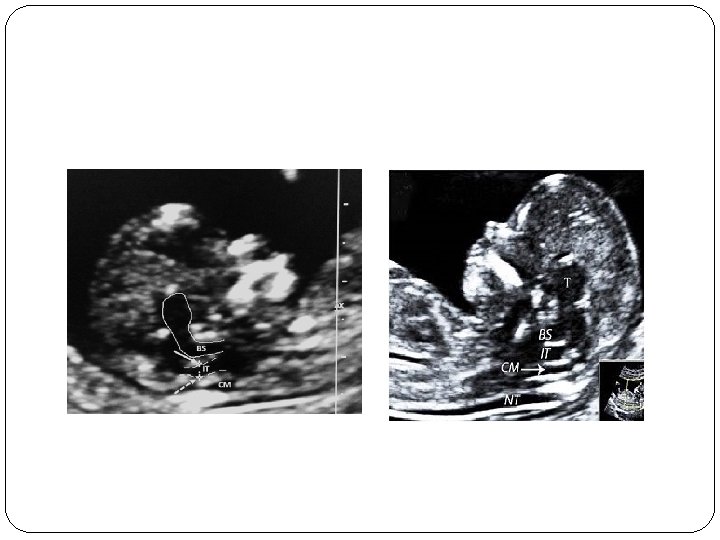

IT(Intracerebral Translucency )

IT…. open NTD �One of the major failings of the first trimester fetal ultrasound examination had been the inability to consistently diagnose open neural tube defects other than the exencephaly/ anencephaly sequence �A recently described intracranial marker [intracerebral translucency (IT)] may overcome this deficiency. � The fetal image required to evaluate the IT is identical to those needed for the NT, NB and FMF angle evaluation

� A magnified midline view of the fetal head and upper thorax is obtained and the following intracranial structures need to be visualized: hypoechoic regions of the thalamus, the pons (brain stem) and the medulla oblongata � The IT represents the fluid filled fourth ventricle, which is located posteriorly to the pons. � The combination of the posterior border of the pons and the floor of the fourth ventricle is seen as a single thin echogenic line, which forms the anterior border of the IT. � The posterior border of the IT is the roof of the fourth ventricle. This is seen also as a relatively thin

� The proposed mechanism for this finding is similar to that of the Chiari type II malformation (banana sign) seen in second trimester fetuses with spina bifida aperta: decreased pressure in the subarachnoid spaces leading to the caudal displacement of the brain. � Measuring the IT does not provide additional information. Therefore, the IT is simply reported as present or absent. � It would be premature to state that the absence or presence of IT has the same predictive value as the intracranial findings in the second trimester. However, the absence of the IT should lead to an extremely careful ultrasound evaluation of the spine at the time of the first trimester ultrasound. If the appearance of the spine is normal on the initial scan, the fetus should be reexamined at approximately 16 weeks. A 20 week scan should also be performed if the 16 week scan is normal.

� So normally, the ratio of the BS to the BSOB will range from 0. 8 at 11 weeks to somewhere around 0. 7 at 14 weeks. In fetuses with open spina bifida, because of the posterior shift of the brain, the BS appears relatively enlarged and shifted backwards, so the BS to BSOB (BS/ BSOB) ratio is increased and it is usually more than one

� Transvaginal scan rather than transabdominal scan. � In axial plane, the midbrain is visualized just caudal to the plane in which the biparietal diameter is measured. � In the axial oblique plane, we see the two thalami with third ventricle in between. Posterior to thalami are the two cerebral peduncles with the aqueduct of Sylvius (AOS) in between. � Under normal conditions, transition from the cerebral peduncles to the thalami follows an acute angle and there is some distance between the AOS and the occipital bone.

� In fetuses with open spina bifida, due to the posterior shift of the midbrain, the cerebral peduncles distort and become juxtaposed to the occipital bone, with parallelism of the cerebral peduncles. The AOS at this gestation is seen as a prominent ‘echogenic box’ traversing the midbrain. � The AOS to occiput distance is measured from the posterior border of the AOS to the anterior border of the occiput in the axial plane (inner to inner) and it ranges from 1. 7 mm (at CRL of 45 mm) to 3. 7 mm (at CRL of 84 mm). This distance will be reduced in fetuses with open spina bifida because of juxtaposition of the midbrain to the occiput.